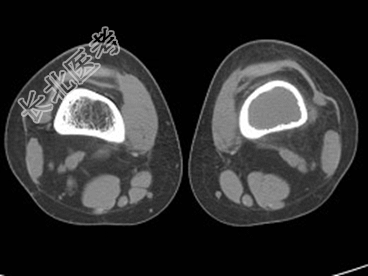

- [材料题] 患者,男,33岁,左股骨肿块半年余,无明显症状,查体一般情况良好。

- 简答题1、结合所提供的图像,该患者诊断为?

- 1、该患者诊断是?2、该疾病的治疗原则是